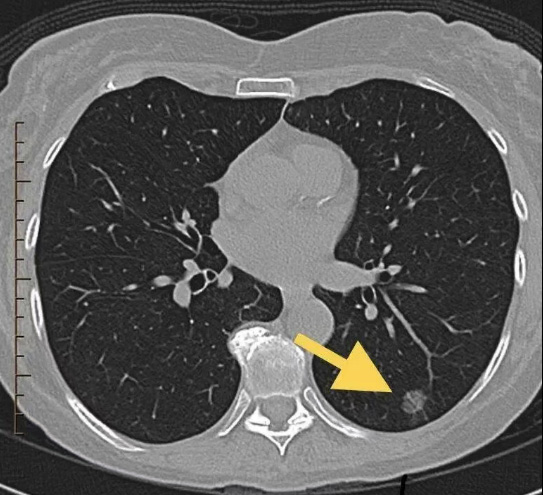

肺結(jié)節(jié)通常指直徑小于3厘米的局灶性、類圓形、密度增高的實(shí)性或亞實(shí)性肺部病變,這些病變?cè)谟跋裆喜话橛蟹尾粡垺⒎伍T淋巴結(jié)腫大或胸腔積液等征象。

采用低劑量薄層CT掃描(LDCT)